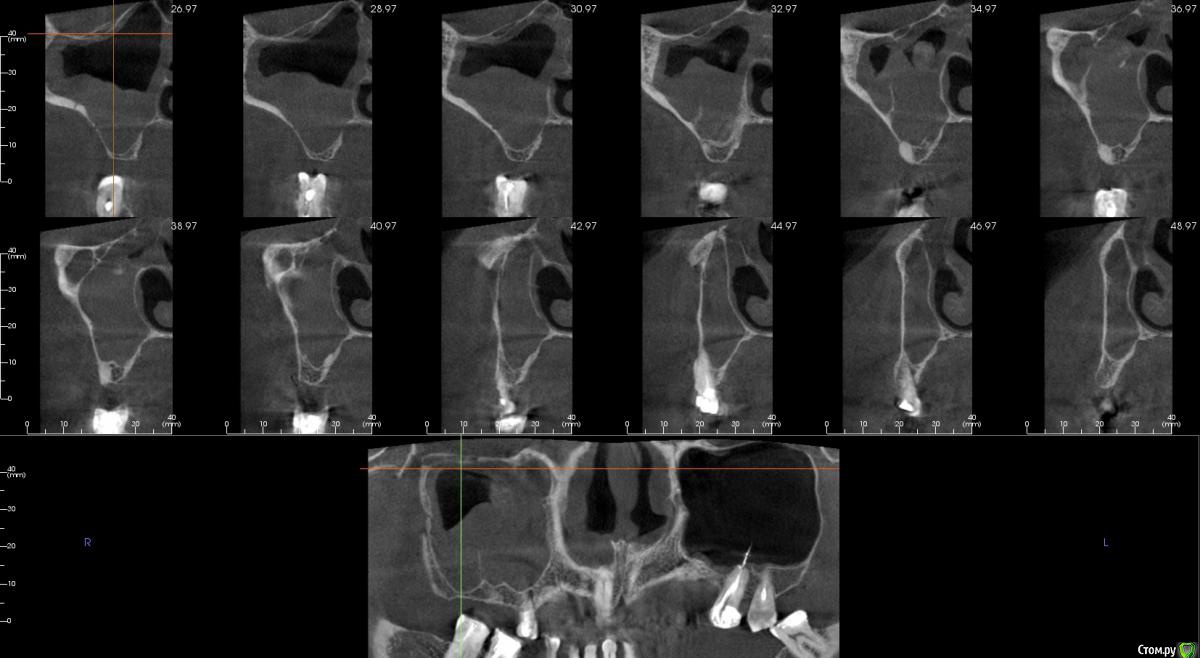

Irouil Опубликовано 16 апреля, 2018 Поделиться Опубликовано 16 апреля, 2018 Имхо - нет. ЛОР КТ смотрел вообще? Тут может быть что угодно, от уровня жидкости до инвертированной папиломы. Ссылка на комментарий

kamranchick Опубликовано 16 апреля, 2018 Автор Поделиться Опубликовано 16 апреля, 2018 Смотрел, и такое заключение дал. вот меня и смутило, в верхней трети около соустя вообще вкрапления какие то есть )) Ссылка на комментарий

Irouil Опубликовано 16 апреля, 2018 Поделиться Опубликовано 16 апреля, 2018 Смотрел, и такое заключение дал. вот меня и смутило, в верхней трети около соустя вообще вкрапления какие то есть ))Больше всего похоже на грибковое тело, и вкрапления эти намекают, и контуры затенения. Пунктировать не стал ЛОР это? 1 Ссылка на комментарий

kamranchick Опубликовано 16 апреля, 2018 Автор Поделиться Опубликовано 16 апреля, 2018 Больше всего похоже на грибковое тело, и вкрапления эти намекают, и контуры затенения. Пунктировать не стал ЛОР этоОтправил для санации, он написал вот это только( что ретенционная, но потом я внимательно начал крутить туда сюда и вот засомневался Ссылка на комментарий

Irouil Опубликовано 16 апреля, 2018 Поделиться Опубликовано 16 апреля, 2018 По большому счету; какая разница то? Вы же пациентку ради синус лифта (насколько я понимаю) отправляли, в таких условиях его не сделать. Там даже если соустье толщиною с пенис Трампа будет, все равно его ткани+отек перекроют после синуса. Так или иначе пазуху надо оперировать, только если ЛОР не считает что ретенционная киста - одонтогенная и пройдет при санации первичного очага) Ссылка на комментарий

kamranchick Опубликовано 19 апреля, 2018 Автор Поделиться Опубликовано 19 апреля, 2018 а как полез? Ну вот напишите своему ЛОРу, что надо посоветоваться ) ну в мягкой форме короче ) пусть лечитсоздал окно, прокол- вытался выкачать жидкость, ничего особо не выходило, создал отверстие больше, начал мыть, там хренотень всякая, но и чистил мыл, окно закрыл и ушился) Ссылка на комментарий

Bier Опубликовано 19 апреля, 2018 Поделиться Опубликовано 19 апреля, 2018 без эндоскопа, хотя бы самого простого за 200 баксов, сложно рассчитывать, что через маленькое окно вы убрали грибковое тело 1 Ссылка на комментарий

kamranchick Опубликовано 19 апреля, 2018 Автор Поделиться Опубликовано 19 апреля, 2018 без эндоскопа, хотя бы самого простого за 200 баксов, сложно рассчитывать, что через маленькое окно вы убрали грибковое телода конечно не убрал)) я то думал что там кистень Ссылка на комментарий